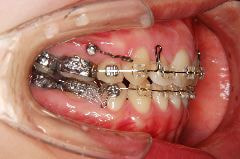

歯科矯正用アンカースクリューの使用例

例1)